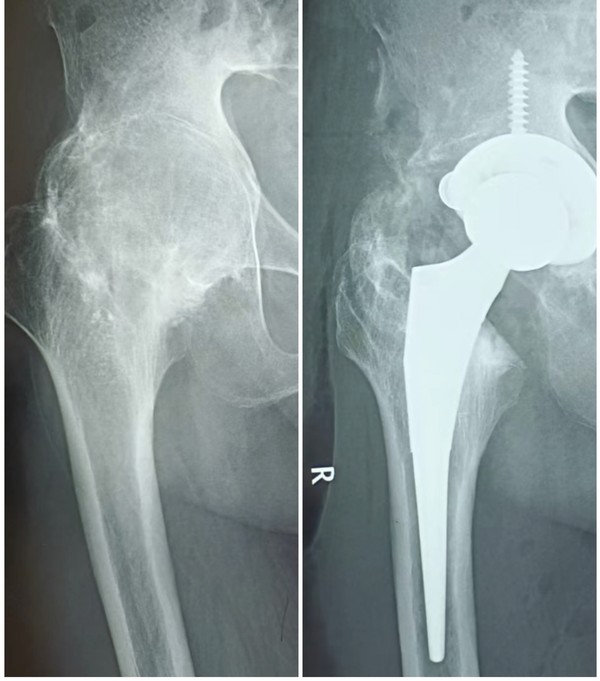

近日,我院为一名右髋关节45年一直不能动的张大爷实施融合髋全髋关节置换术,术后三天患者就可以在助行器辅助下行走了。

患者张大爷,65岁,因45年前外伤致右侧髋关节融合,不能正常坐凳子,不能下蹲,严重影响生活,多次就诊保守治疗无效,我院骨一科副主任夏百红接诊后决定予以收住入院手术治疗。因该手术难度大,术中暴露及关节周围软组织松解困难,入院后甘德军主任组织科内讨论及风险评估,在做好充分术前准备的情况下,在院麻醉科、手术室的协助下,夏百红副主任、甘德军主任凭借着丰富的经验和细致的操作,为患者行右侧人工全髋关节置换手术,手术过程顺利。

术后经骨一科医护团队的精心治疗护理,患者的病情一天天好转,右侧髋关节活动度较术前明显改善,生活质量得到大幅提高,患者对手术效果满意,取得了较好的临床效果。